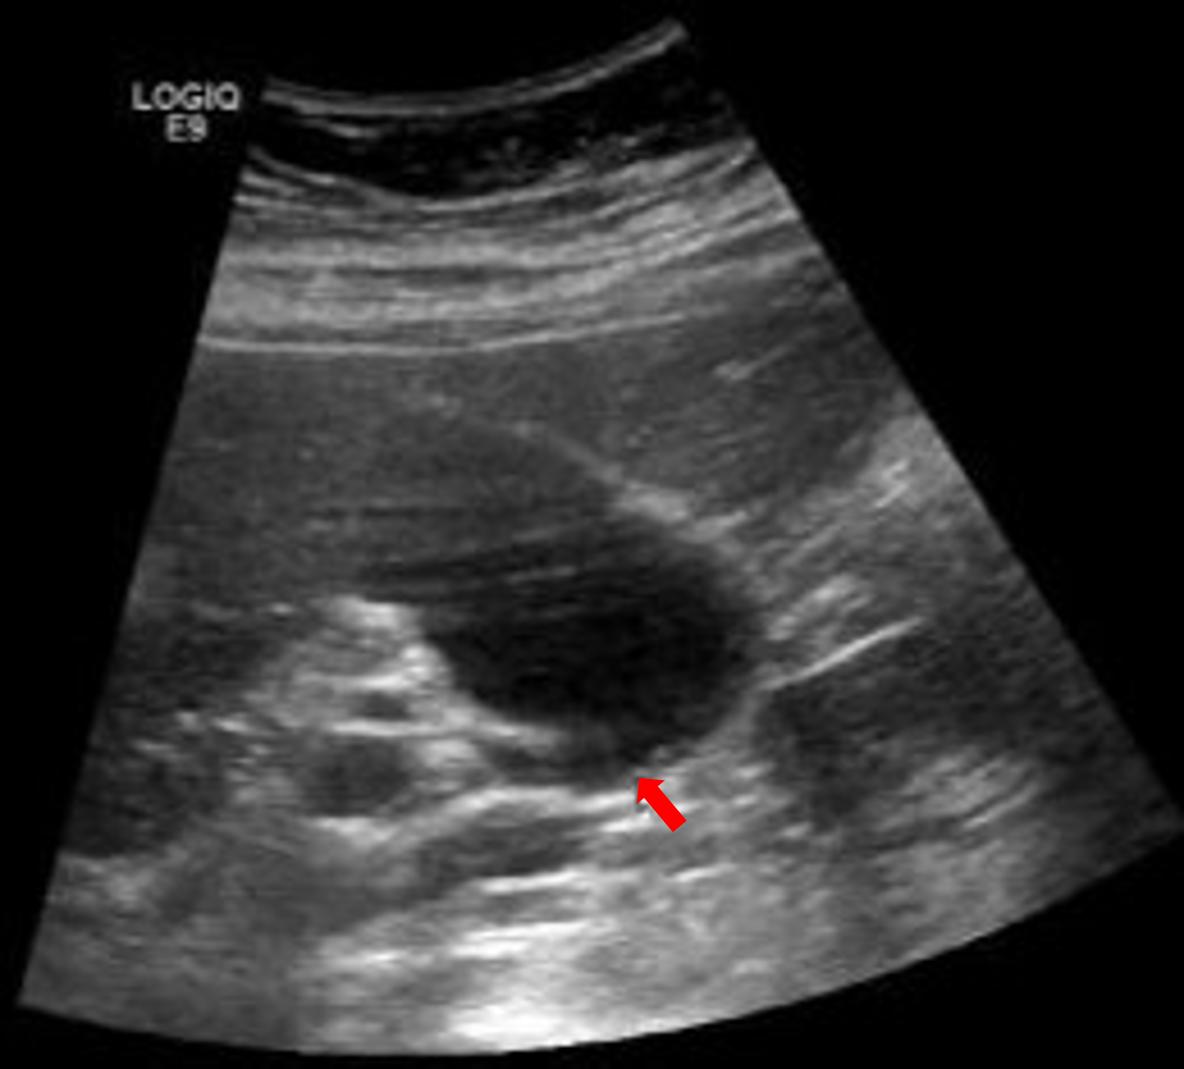

图三,空腹患者的胆囊,胆囊充盈良好,内壁显示很清楚,即使这种不到2mm的小结石,仔细观察也是可以发现的。

图五,这个红笔圈出的是餐后的胆囊,胆汁排出了一部分,相比之下,这个胆囊壁的褶皱之间有没有息肉和结石,就不好说了。